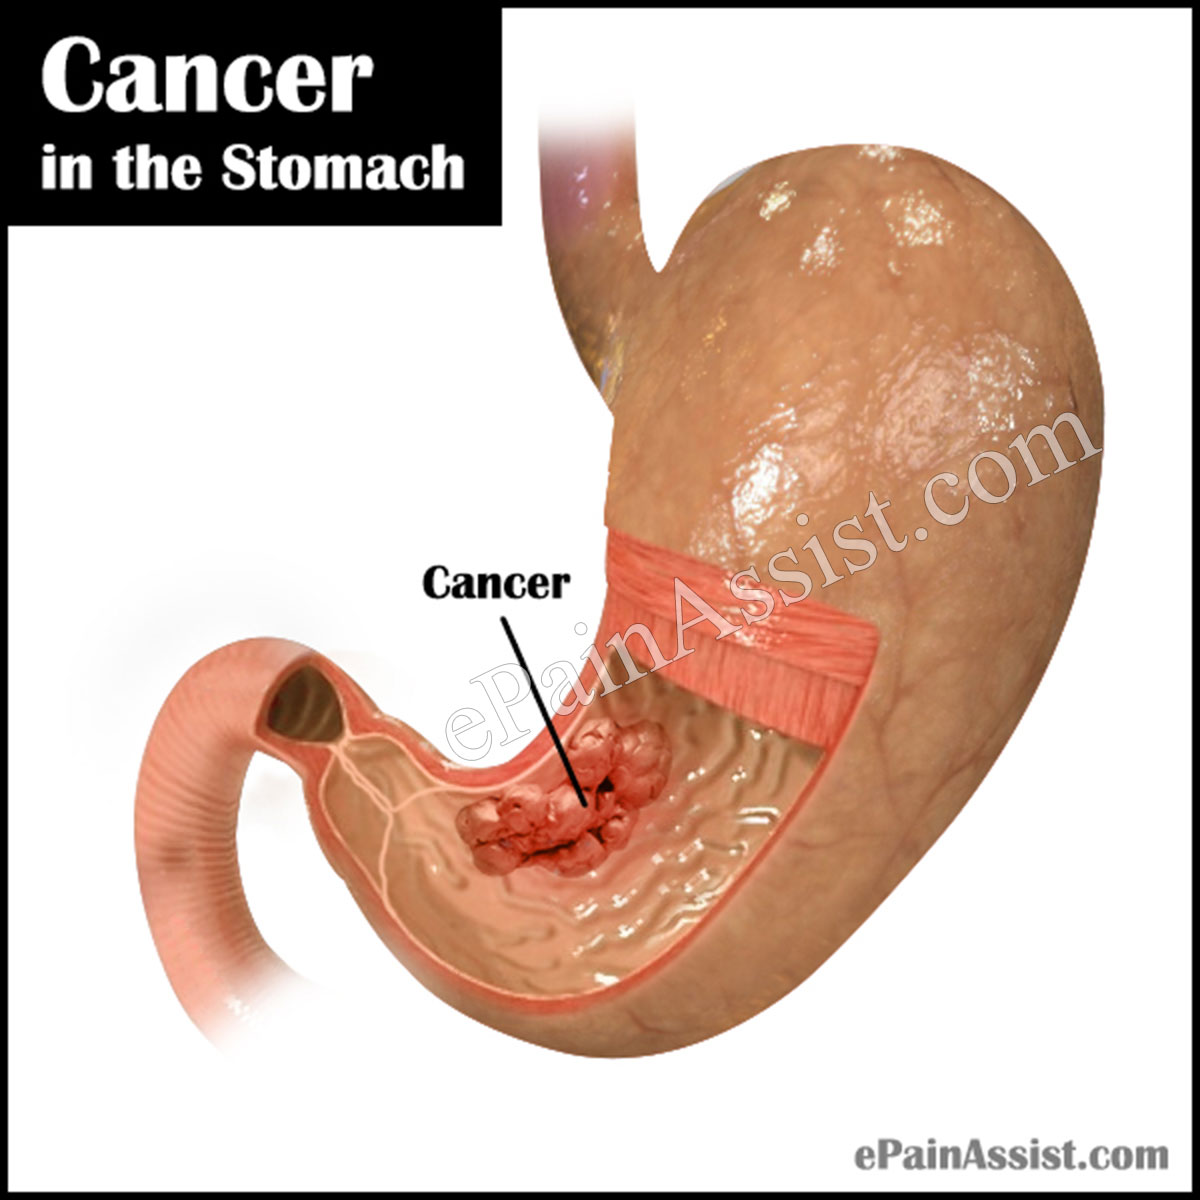

Cancer in the Stomach|Causes|Symptoms|Stages|Treatment|Survival Rate

Stomach Cancer

Stomach Cancer